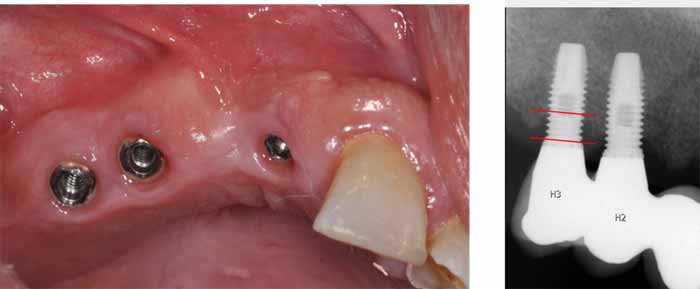

作業部会が発足して以来、SKRIは形になり、これまでグループは定められたスケジュールに沿って活動してきました。パイロット報告書の目標を達成するため、昨年は、スウェーデン保健福祉庁(社会庁:National Board of Health and Welfare)の歯科医療に関する国家ガイドラインに基づいた登録指標に関する作業が行われ、Carita医療記録システムは技術的な解決策を開発しました。これにより、インプラント部品上のQRコードのスキャンが可能になりました。正確かつ関連性の高い情報を医療記録システムに登録し、SKaPaにエクスポートすることができます。このデータを使用して、インプラントの機能に関する関連情報を入手することができます。Caritaは2022年春に最初のテスト版を開発、実装しました。小規模なパイロットレポートは、2022年秋に議会に提出される予定です。現在の計画では、この医療記録システムのさらなる開発を予定しています。これは、すべての医療記録システムがこの開発を受け入れることを目標とした技術的なソリューションです。SKRIは、スウェーデンの歯科医療を未来へと導きます。